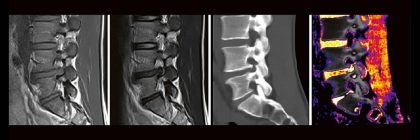

Professor Dr. med. Marc Brockmann WEITERENTWICKLUNGEN VON KOPF BIS FUSS BEIM VC Oberstarzt Dr. med. Stephan Waldeck DEEP-LEARNING-REKONSTRUKTION IN DER NEURORADIOLOGIE Die CT ist ein essentielles Routine-Verfahren in der Neuroradiologie. Weiterlesen …